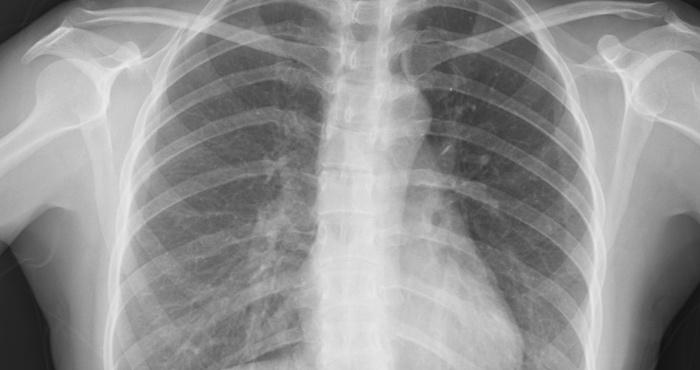

Ảnh y khoa (năm 1895)

Chụp X-quang là kỹ thuật chẩn đoán h́nh ảnh y khoa đầu tiên trong lịch sử. Năm 1895, nhà vật lư học người Đức Wilhelm Conrad Rӧntgen t́nh cờ phát hiện kỹ thuật này khi đang thí nghiệm cho ḍng điện qua các ống tia âm cực. Chỉ qua một đêm, phát hiện của ông đă thay đổi hoàn toàn ngành y học. Năm 1896, bệnh viện Glasgow mở khoa X-quang đầu tiên trên thế giới.

Siêu âm được đưa vào khoa chẩn đoán h́nh ảnh từ năm 1955. Các bác sĩ dùng sóng âm thanh tần số cao để tạo ra h́nh ảnh kỹ thuật, hỗ trợ chẩn đoán bệnh.

Năm 1967, kỹ thuật chụp cắt lớp vi tính (CT) được phát minh, sử dụng tia X và máy tính để chẩn đoán nhiều loại bệnh khác nhau. Máy chụp CT trở thành công cụ chẩn đoán quan trọng trong y học hiện đại.

Công nghệ chụp cộng hưởng từ (MRI) được Paul Lauterbur phát minh năm 1973. Dữ liệu cộng hưởng từ hạt nhân tạo ra h́nh ảnh chi tiết trong cơ thể, phát hiện khối u, u nang, tổn thương năo, tủy sống và một số vấn đề về tim, gan.